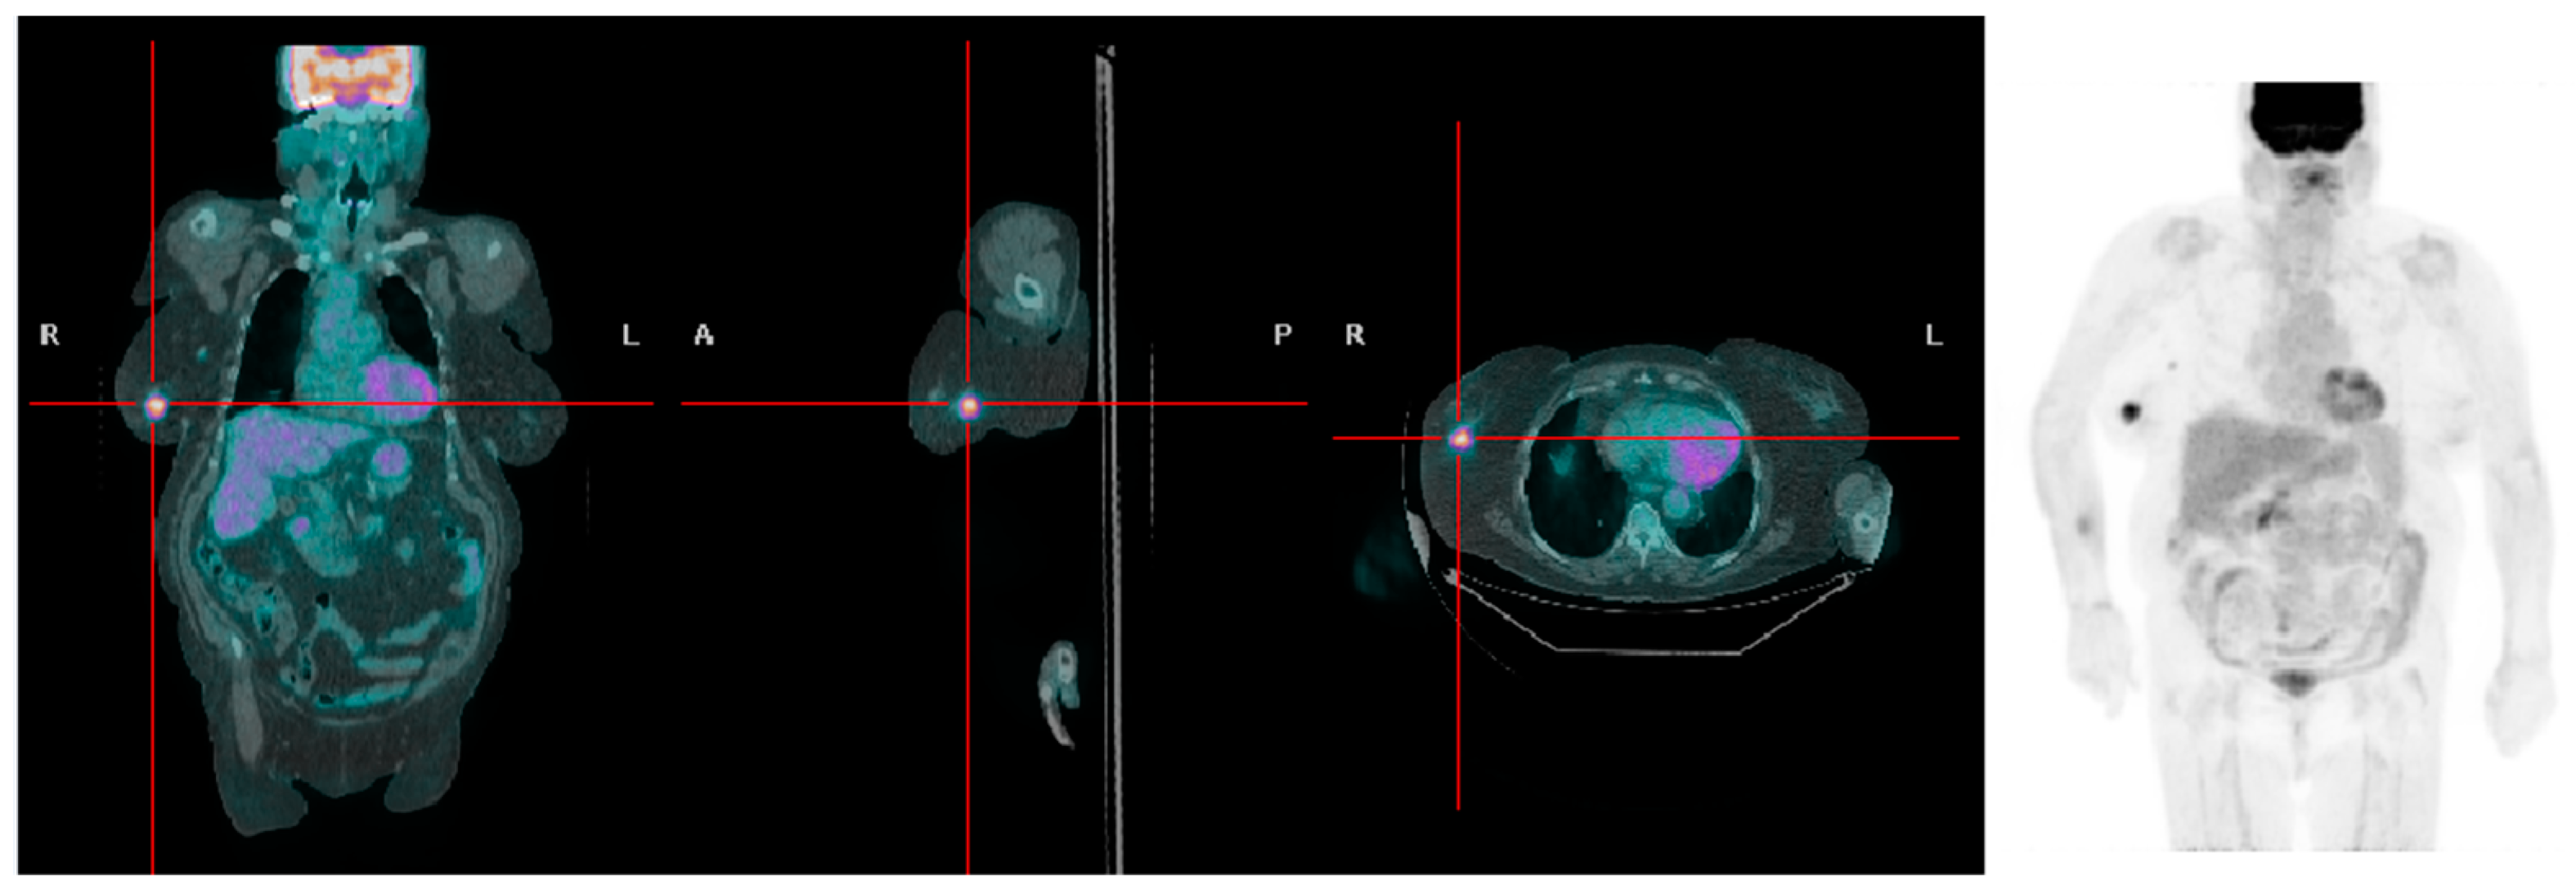

There were 48 recurrences at the follow-up (35 in the overweight group and 13 in patients with normal weight). The chi-square test demonstrated a higher frequency of recurrences in overweight women compared to women with a BMI < 25 kg/m2 (35 vs. 13; p = 0.025). The local and regional recurrence rates were 17.85% and 25% in the overweight patient group and 3% and 12% in the normal weight patient group, respectively. A significantly higher frequency of T_rec (15 vs. 2; p = 0.018) and a higher T_rec SUVmax (4.74 ± 2.90 vs. 1.85 ± 0.63, respectively; p = 0.09; Figure 1 and Figure 2) were found in overweight women compared to women with a BMI < 25 kg/m2. No statistically significant difference between the two groups was found for the frequency of N_rec and M_rec. SUVmax of N_rec was significantly higher in overweight patients compared to patients with BMI < 25 kg/m2 (6.57 ± 4.08 vs. 3.14 ± 1.62, respectively; p = 0.004).

Figure 2.

A patient with high BMI presenting with a right-sided breast tumor with high [18F]FDG uptake (SUVmax 6.3).